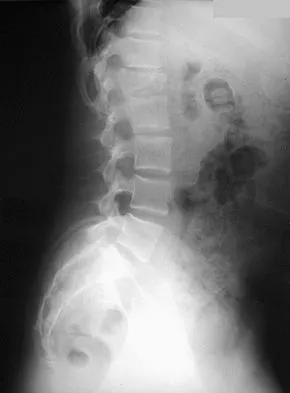

A 50-year-old man reports the onset of back pain and incapacitating pain radiating down his left leg posterolaterally and into the first dorsal web space of his foot 1 day after doing some yard work. He denies any history of trauma. Examination reveals ipsilateral extensor hallucis longus weakness. MRI scans are shown in Figures 19a through 19c. What nerve root is affected?

Detailed Explanation

The MRI scans clearly show an extruded L4-5 disk that is affecting the L5 root on the left side. In addition, the L5 root has a cutaneous distribution in the first dorsal web space. S1 affects the lateral foot, and L4 affects the medial calf. An HS: Principles and Techniques of Spine Surgery. Baltimore, MD, Williams and Wilkins, 1998, pp 98-100.